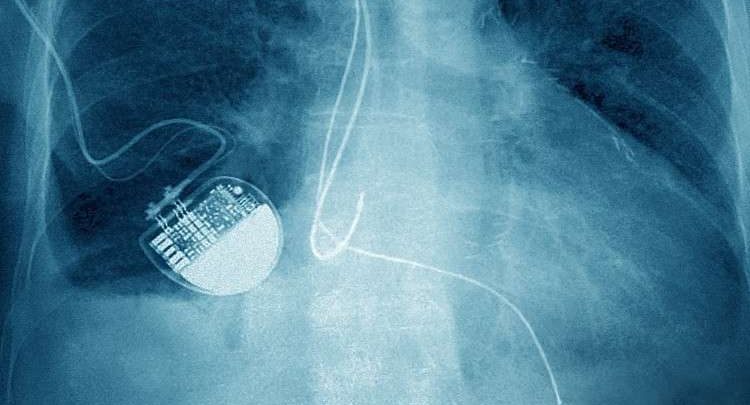

حذرت تقارير جديدة من أن #الهاكرز يمكنهم قتل عدد من المرضى عن طريق إيقاف أجهزة تنظيم ضربات #القلب أو مضخاته.

وتقول الأكاديمية الملكية للمهندسين إن التكنولوجيا الصحية مفتوحة للهجمات الإلكترونية، كما أن الأجهزة المتصلة بالإنترنت مثل أجهزة التلفزيون الذكية والأجهزة المنزلية الذكية أيضا يمكن أن تشكل تهديدا لهؤلاء المرضى.